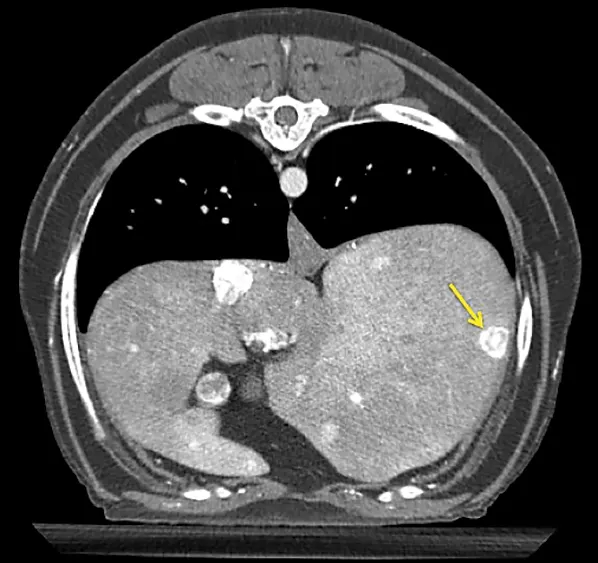

Additional diagnostics were pursued. Abdominal ultrasonography demonstrated an ill-defined and mildly hyperechoic 0.75 × 1.37-cm nodule at the base of the left lobe of the pancreas (Figure 1). Small, well-defined hyperechoic nodules were also found scattered throughout all liver lobes. Three-view thoracic radiographs revealed no significant abnormalities.

Figure 2 Arterial phase CT angiograph image demonstrating a strongly contrast-enhancing pancreatic nodule (arrow)